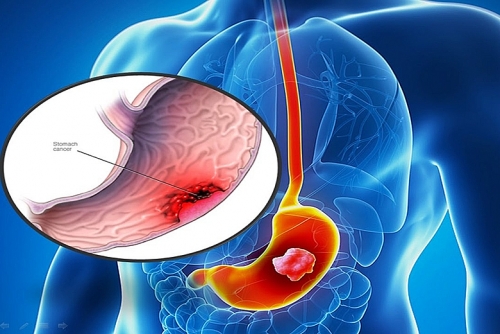

Xét nghiệm máu có phát hiện ung thư dạ dày không?

Xét nghiệm máu có phát hiện ung thư dạ dày không là điều nhiều người thắc mắc khi có dấu hiệu bệnh.

Các giai đoạn ung thư dạ dày

Các giai đoạn ung thư dạ dày gồm những gì? Có thể phòng tránh ung thư dạ dày bằng cách nào? Đọc bài viết ngay để nắm rõ thông tin.

Dấu hiệu ung thư dạ dày giai đoạn cuối

Dấu hiệu nào cho biết ung thư dạ dày đã tới giai đoạn cuối? Cần làm gì để phát hiện bệnh sớm?

Cắt ung thư dạ dày sống được bao lâu?

Nếu không may bị ung thư dạ dày, việc phải cắt bỏ một phần dạ dày có thể sẽ xảy ra nếu giai đoạn bệnh nặng. Vậy cắt ung thư dạ dày sống được bao lâu?

Triệu chứng ung thư dạ dày

Triệu chứng ung thư dạ dày gồm những triệu chứng gì? Cần làm gì để phát hiện sớm ung thư dạ dày?